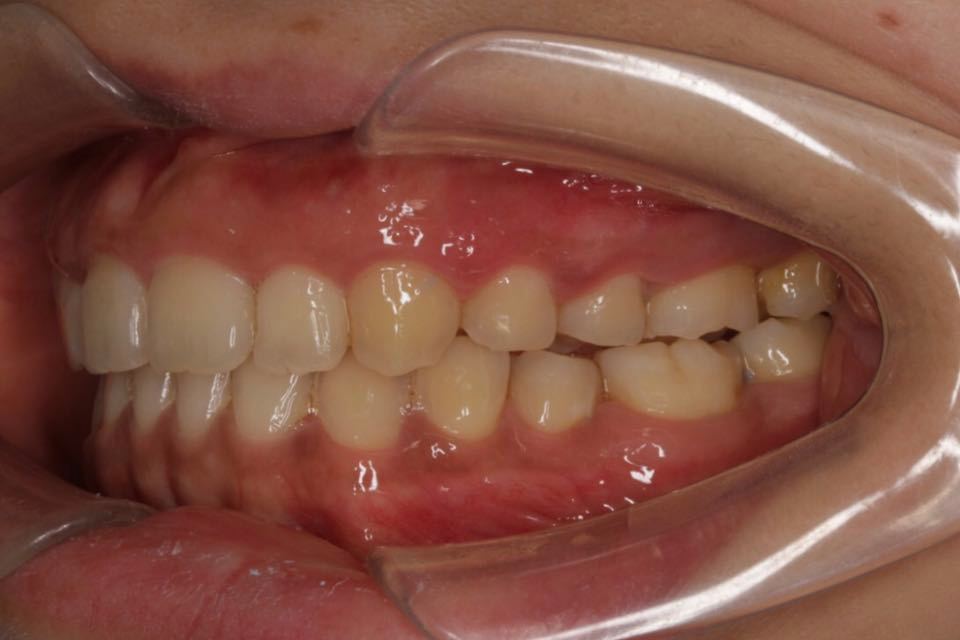

矫正后口内照:

治疗改善:关闭散隙,调整中线。

目前阶段:全口牙齿排列整齐,中线居中。前牙覆合覆盖正常,尖磨牙关系达I类咬合关系。总疗程约18个月。